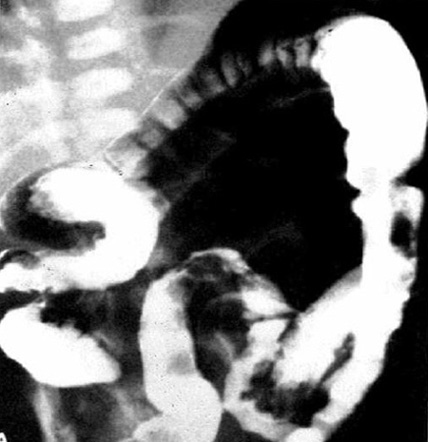

Um enema com contraste realizado com material de contraste hidrossolúvel é o exame de imagem mais valioso para a doença de Hirschsprung. Um enema com contraste é recomendado se a avaliação clínica for suspeita de doença de Hirschsprung ou se houver sinais de obstrução distal na radiografia. Uma relação retossigmoide (diâmetro máximo do reto dividido pelo diâmetro máximo do cólon sigmoide durante o enema com contraste) de <1 é altamente sugestiva de doença de Hirschsprung. Outros achados sugestivos incluem contraste retido por >24 horas, irregularidade da mucosa ou microcólon.[48] Uma zona de transição pode ser observada no enema com contraste, mas isso pode ser menos óbvio em neonatos.[49] Uma zona de transição no enema com contraste pode ajudar no planejamento cirúrgico, mas deve-se observar que a zona de transição radiográfica pode não se correlacionar com a zona de transição histológica.[50] O enema com contraste pode demonstrar irregularidade da mucosa no cólon distal aganglionar e pode mostrar uma zona de transição entre o cólon distal aganglionar de menor calibre e o cólon ganglionar proximal dilatado.[Figure caption and citation for the preceding image starts]: Enema de bário realizado em um neonato com doença de Hirschsprung. Frequentemente, as alterações clássicas não são evidentes no período neonatalCorman ML. Colon and rectal surgery. 5ª ed. Philadelphia, PA: Lippincott Williams and Wilkins; 2005:555-603; usado com permissão. [Citation ends].